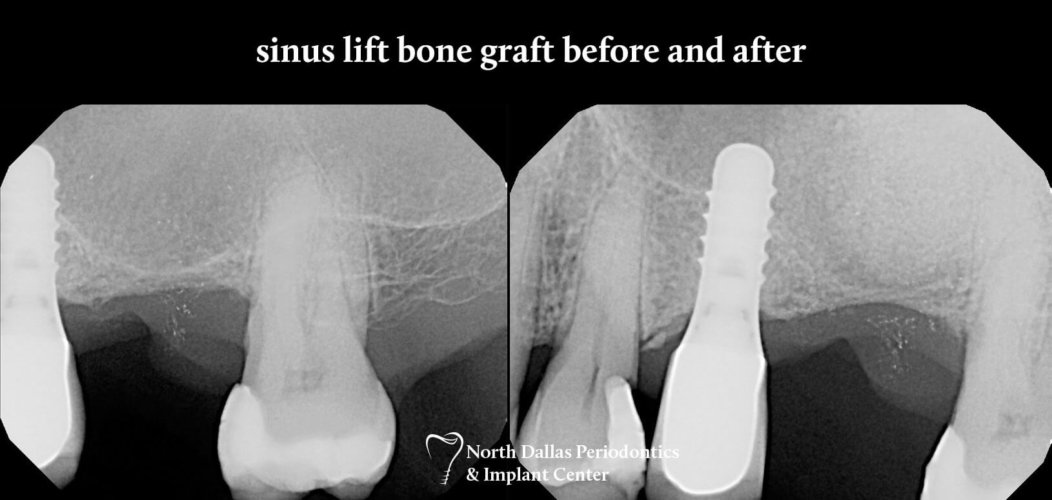

From www.ndperio.com

Dental Implants Gallery North Dallas Periodontics & Implant Center Periodontist Sinus Lift John thousand iv describes what you should do after sinus lift surgery, and what you can expect during your sinus lift recovery experience. It involves “lifting” the sinus membrane to make more room for the implants. Expert tips for smooth sinus lift recovery journey after completing surgery. Over time, the sinus expands taking over the bone space around tooth roots.. Periodontist Sinus Lift.